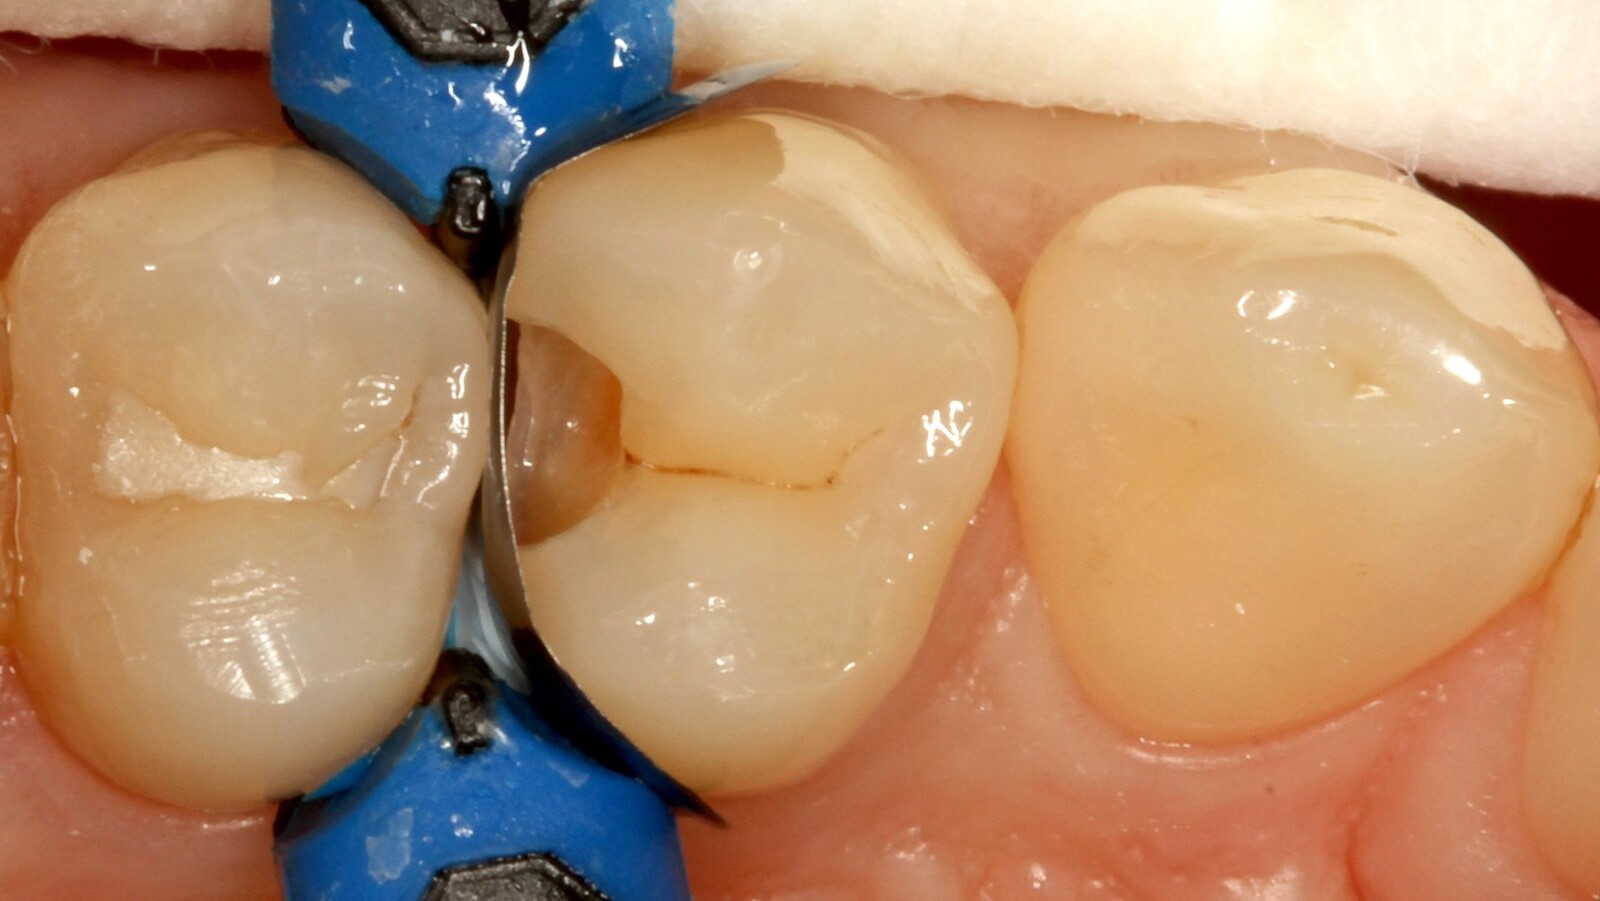

Professor Ernst first identified the hidden caries and opened the carious lesion to show the patient the problem (Fig. 1-2). He then excavated the caries, prepared the cavity and placed a sectional matrix (Fig. 3) before sealing the cavity with adhesive (Fig. 4). In a single step, he filled the cavity with Venus Bulk Flow ONE (Fig. 5). Once the restoration was completed, Prof. Ernst polished it (Fig. 6) and took a control radiograph, which also shows the excellent radiopacity of Venus Bulk Flow ONE (Fig. 7).